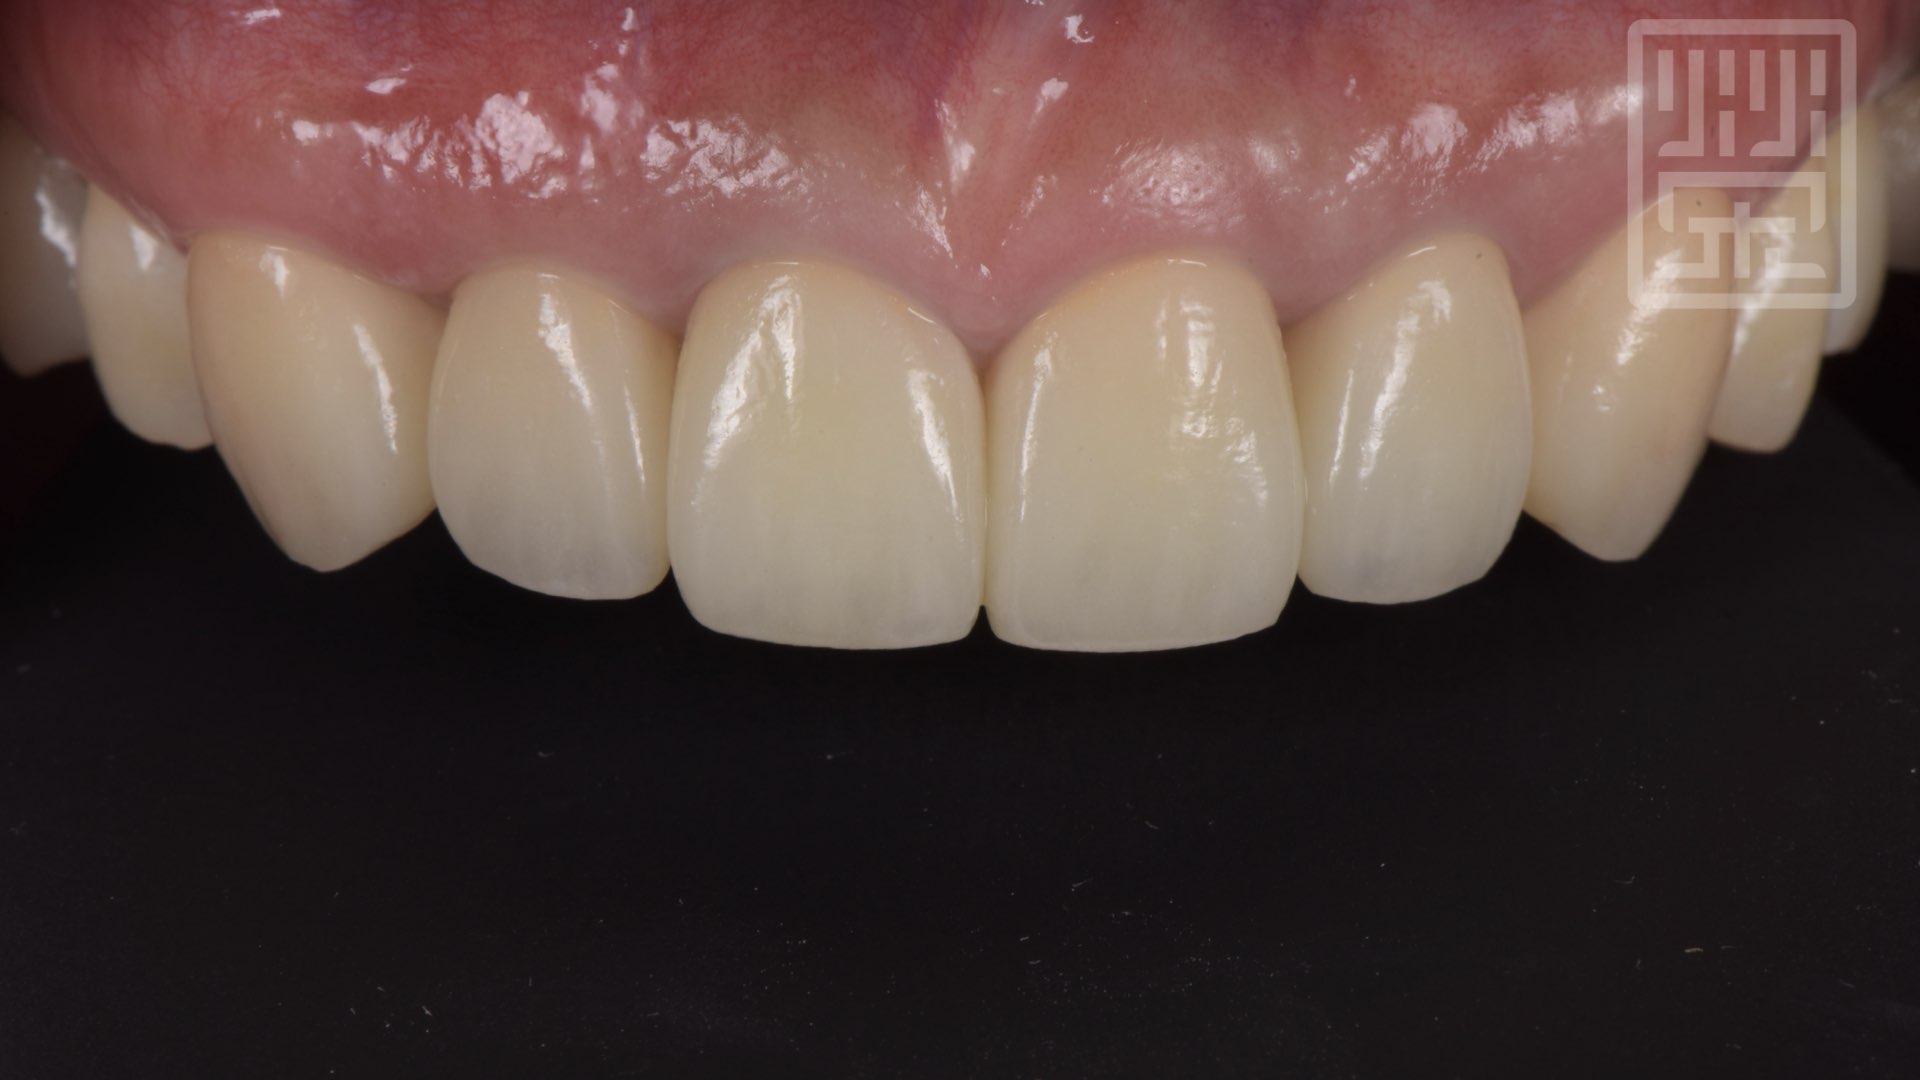

植牙全瓷冠修復

植牙全瓷冠